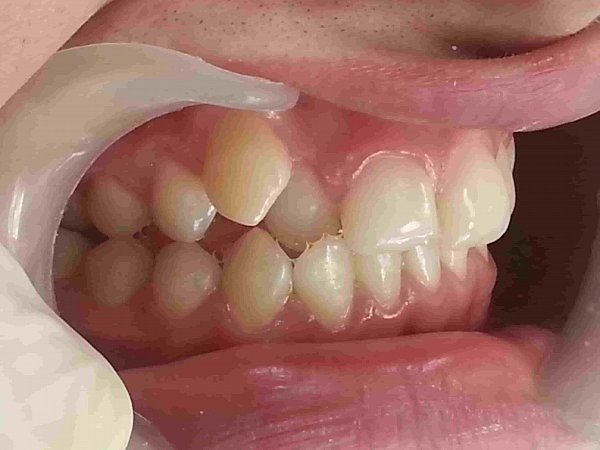

Пациентка 16 лет. Жалобы на неправильное положение зубов, нарушение прикуса.

Ортодонтического лечение проводилось на

Диагноз: Мезиальная окклюзия, тенденция к вертикальной резцовой дизокклюзии, скучное положение зубов.

Фактический срок лечения 25 месяцев